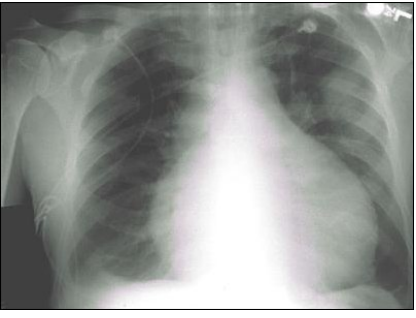

30 下列何者不是急性腎衰竭病人接受緊急血液透析治療的適應症?(一律給分) (A)BUN 120 mg/dL,creatinine 2.5 mg/dL (B)血鉀值大於 7 mEq/L,且 Kayexalate(sodium polystyrene sulfonate)治療效果不佳 (C)心包膜積水 (D)肺水腫

65 一位 67 歲男性,主訴兩週來漸發性呼吸困難,病患抽菸 50 年,近半年來常感倦怠,常咳嗽且併有 濃痰。身體診查血壓 90/60 毫米汞柱,呼吸速率每分鐘 30 下,脈搏每分鐘 100 下,心臟的聽診發現 心音變小(distant heart sound),但無心雜音,在鼻管通氧 2 公升/分鐘下,動脈血氧飽和度 SaO2: 93%。胸部 X 光如下: 下列敘述何者錯誤?

(A)患者之頸靜脈怒張 (B)患者血壓呼氣時收縮壓下降幅度超過 10 毫米汞柱 (C)患者心電圖檢查之肢導極及胸前導極均呈低電壓 (D)下一步應考慮安排心臟超音波檢查確診